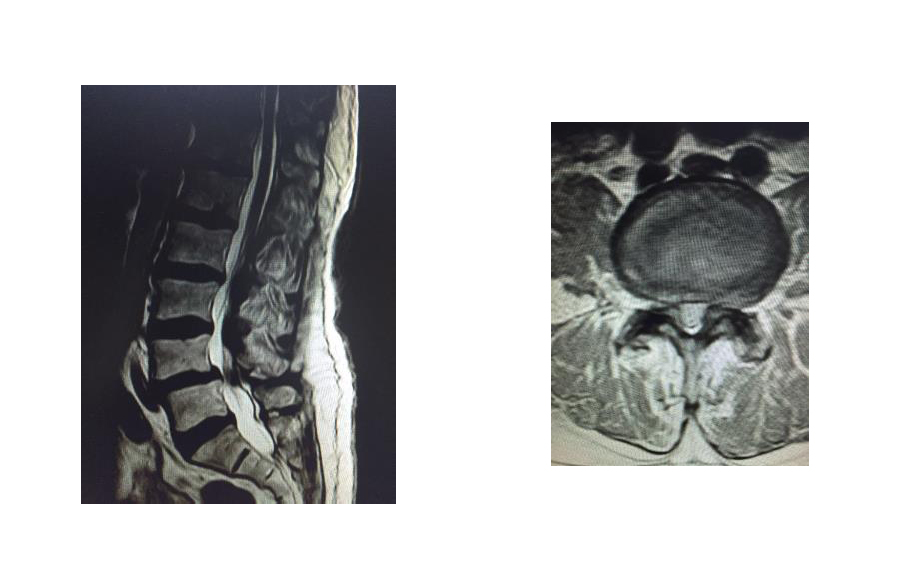

Hernia discal que causan compresión en una raíz nerviosa

Habitualmente causan mucho dolor lumbar, de tipo ciática, con debilidad para caminar y problemas de sensibilidad en los pies.

Requiere una valoración con estudio de imagen para determinar su manejo.